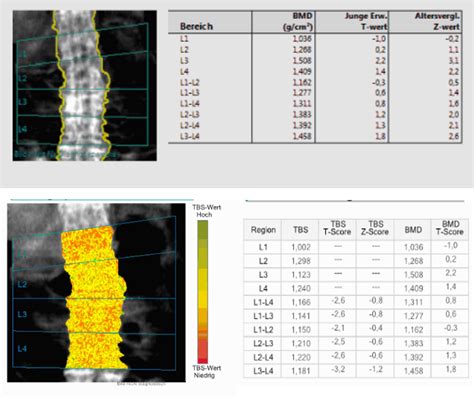

The Trabecular Bone Score is an analytical tool that integrates with existing DEXA scans to evaluate the texture of the lumbar spine. It analyzes the pixel variations in the image to provide an indirect measurement of trabecular microarchitecture. Essentially, while BMD tells us how much bone is there, the TBS tells us about the quality and structural arrangement of that bone.

The process of obtaining a TBS is remarkably simple because it does not require additional radiation or a separate scanning appointment. Instead, it is a software-based analysis performed on the images already captured during a standard lumbar spine DEXA scan.

• Image Acquisition: A routine lumbar spine DEXA scan is performed.

• Software Processing: The TBS software analyzes the gray-level texture of the DEXA image.

• Data Interpretation: The system produces a numerical score reflecting the microarchitectural state of the bone.

A higher TBS value generally indicates a stronger, more connected trabecular network, whereas a lower score suggests a degraded, porous structure. This information is vital for patients whose BMD results fall into the "osteopenia" range, as it helps determine if they are actually at a higher fracture risk than the BMD alone indicates.